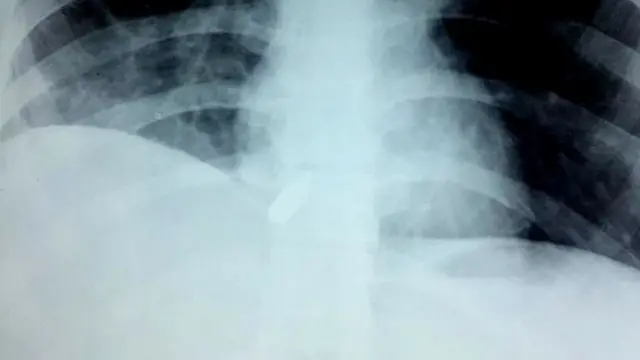

மருத்துவர் ஜாஹித் அலி ஷா, "அறுவை சிகிச்சை தொடங்கியபோது, இந்த அறுவை சிகிச்சை ஐந்து மணி நேரம் நீடிக்கும் என்று எதிர்பார்க்கப்படவில்லை. நாங்கள் அவருடைய மார்பைத் திறந்தபோது, தோட்டா சிக்கிக் கொண்டிருக்கும் என்று நாங்கள் எதிர்பார்த்த இடத்திலிருந்து அறுவை சிகிச்சையைத் தொடங்கினோம். அந்தப் பெண்ணின் இதயத்தைக் கையால் தொட்டபோது, அந்த தோட்டா இதயத்தில் நுழைந்தது என்பதை புரிந்துகொண்டேன்," என்கிறார்.

"எக்ஸ்-ரே எடுத்துப் பார்த்ததில், இதயத் துடிப்போடு தோட்டாவும் மேலேயும் கீழேயும் நகர்ந்தது தெரிந்தது. ஆறு மாதமாக இவர் இதை அனுபவித்து வந்ததால் எனக்கு அந்தப் பெண் குறித்து அதிக கவலை ஏற்பட்டது."

அவர் தோட்டா இருக்கும் இடத்தை அடைந்து அதை வெளியே எடுத்தபோது, நோயாளியின் இரத்த அழுத்தம் பதினைந்து வினாடிகளுக்குக் குறைந்து விட்டது என்று கூறினார். அப்போது, அவரது இதயப் பைகளில் ஒன்றில் அதிக ரத்த இழப்பு ஏற்பட்டதாகவும் அந்த பதினைந்து வினாடிகள் மிகவும் ஆபத்தானவை என்றும் அவர் கூறினார்.